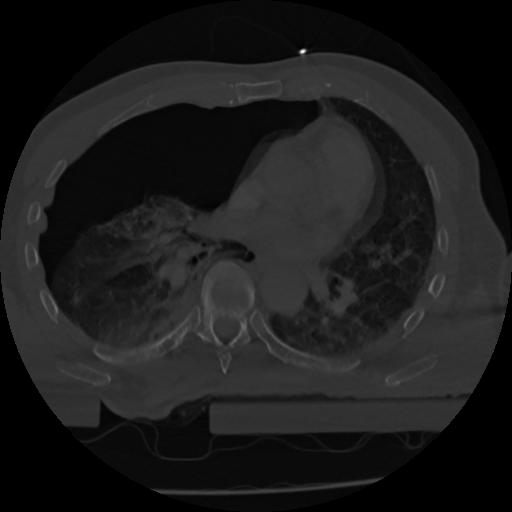

22 ANGIO,CE,Vol,0.5,ANGIO,,